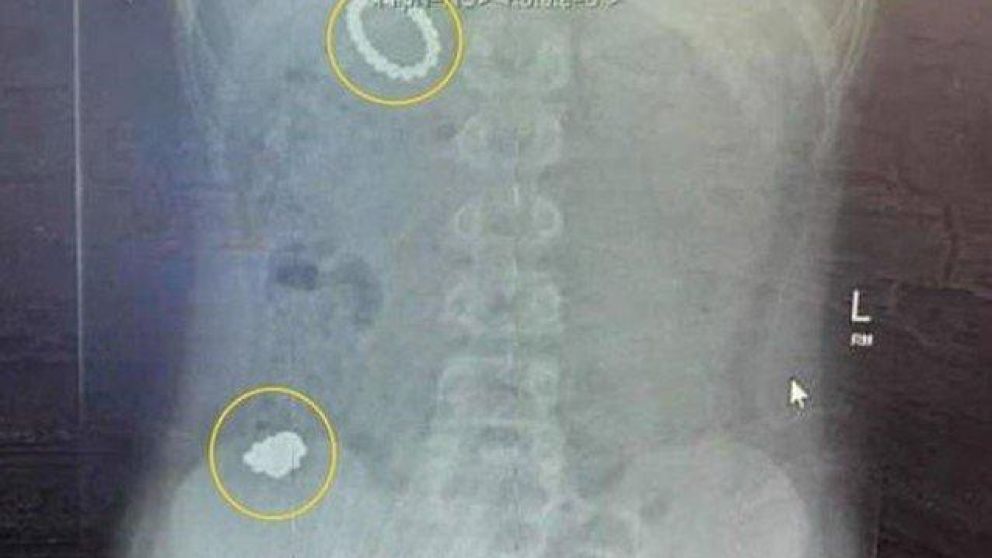

Cuando su mamá lo llevó al hospital, los médicos le hicieron una radiografía y se sorprendieron al encontrar 54 pequeños juguetes magnéticos en su estómago e intestino. Como los especialistas temían que las bolitas imantadas pudieran dañar órganos vitales, Rhiley debió ser intervenido de urgencia, en una cirugía que se extendió por seis horas para poder extraerle los objetos.

El niño había pedido los juguetes magnéticos para Navidad y luego compró las bolas magnéticas él mismo, con el dinero que había ahorrado. Ingirió un lote el 1° de enero y un segundo el 4 de enero. Cuando ninguno de los imanes pasó por completo a través de su sistema digestivo, Rhiley se despertó a las 2 de la madrugada del 5 de enero y le avisó a su mamá, quien enseguida lo llevó al Salford Royal Hospital, pero los médicos lo enviaron al Royal Manchester Children’s Hospital en ambulancia luego de examinar la radiografía.

“Me quedé atónita, sin palabras cuando escuché el número que se había tragado. Los médicos adivinaron alrededor de 25-30 bolitas en la radiografía, pero después de la cirugía dijeron que tenía 54”, relató la mujer de 30 años.